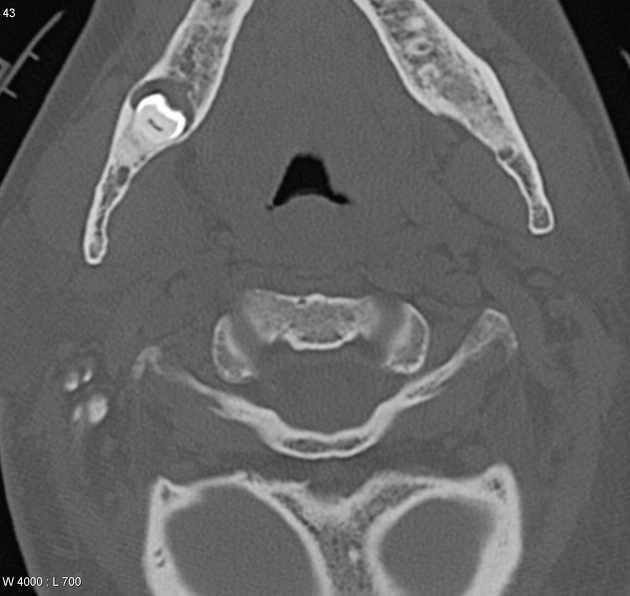

Thoái hóa khớp thái dương hàm (Osteoarthritis of the temporomandibular joint - TMJ OA)

Tràn dịch khớp thái dương hàm (Temporomandibular joint effusion)

Rối loạn chức năng khớp thái dương hàm (Temporomandibular joint - TMJ dysfunction)

Trật khớp thái dương hàm (Temporomandibular joint dislocation)